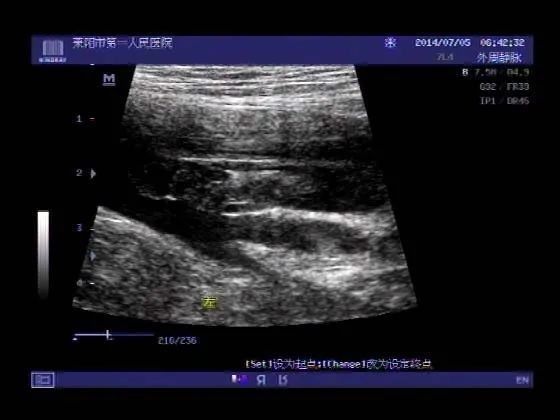

及时至血管外科专科就诊,验血化验D-二聚体和做下肢静脉超声检查,这两个检查可以基本确诊或排除下肢深静脉血栓形成。